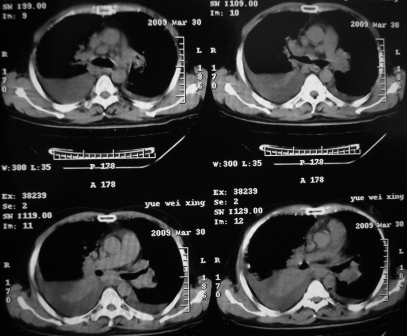

xx 男 43岁

右下叶支气管变窄闭塞,右下叶实变,双肺野弥漫性斑片状影,肺纹理增多增粗,纵隔多发淋巴结肿大,双侧胸水,考虑1双肺继发型结核,右下叶支气管内膜结核,双侧胸水2右下叶中央型肺癌伴右下叶实变,双肺转移,纵隔淋巴转移,双侧胸腔积液3淋巴瘤,请结合病史进一步检查。

病史呢?先考虑----右中央型肺癌继发下叶不张,双肺及纵隔淋巴转移,双侧胸腔积液,心包积液。

不排除---心脏病变所致

右肺下叶支气管中断闭塞,右下肺见不规块影,并胸腔积液,考虑肺中央型肺癌继发下叶不张,\\双侧胸腔积液,心包积液。

考虑右中央型肺癌并下叶不张,双侧胸腔积液,心包积液

右侧中央型肺癌伴右肺下叶不张,双肺及纵隔淋巴转移,双侧胸腔积液,心包积液。